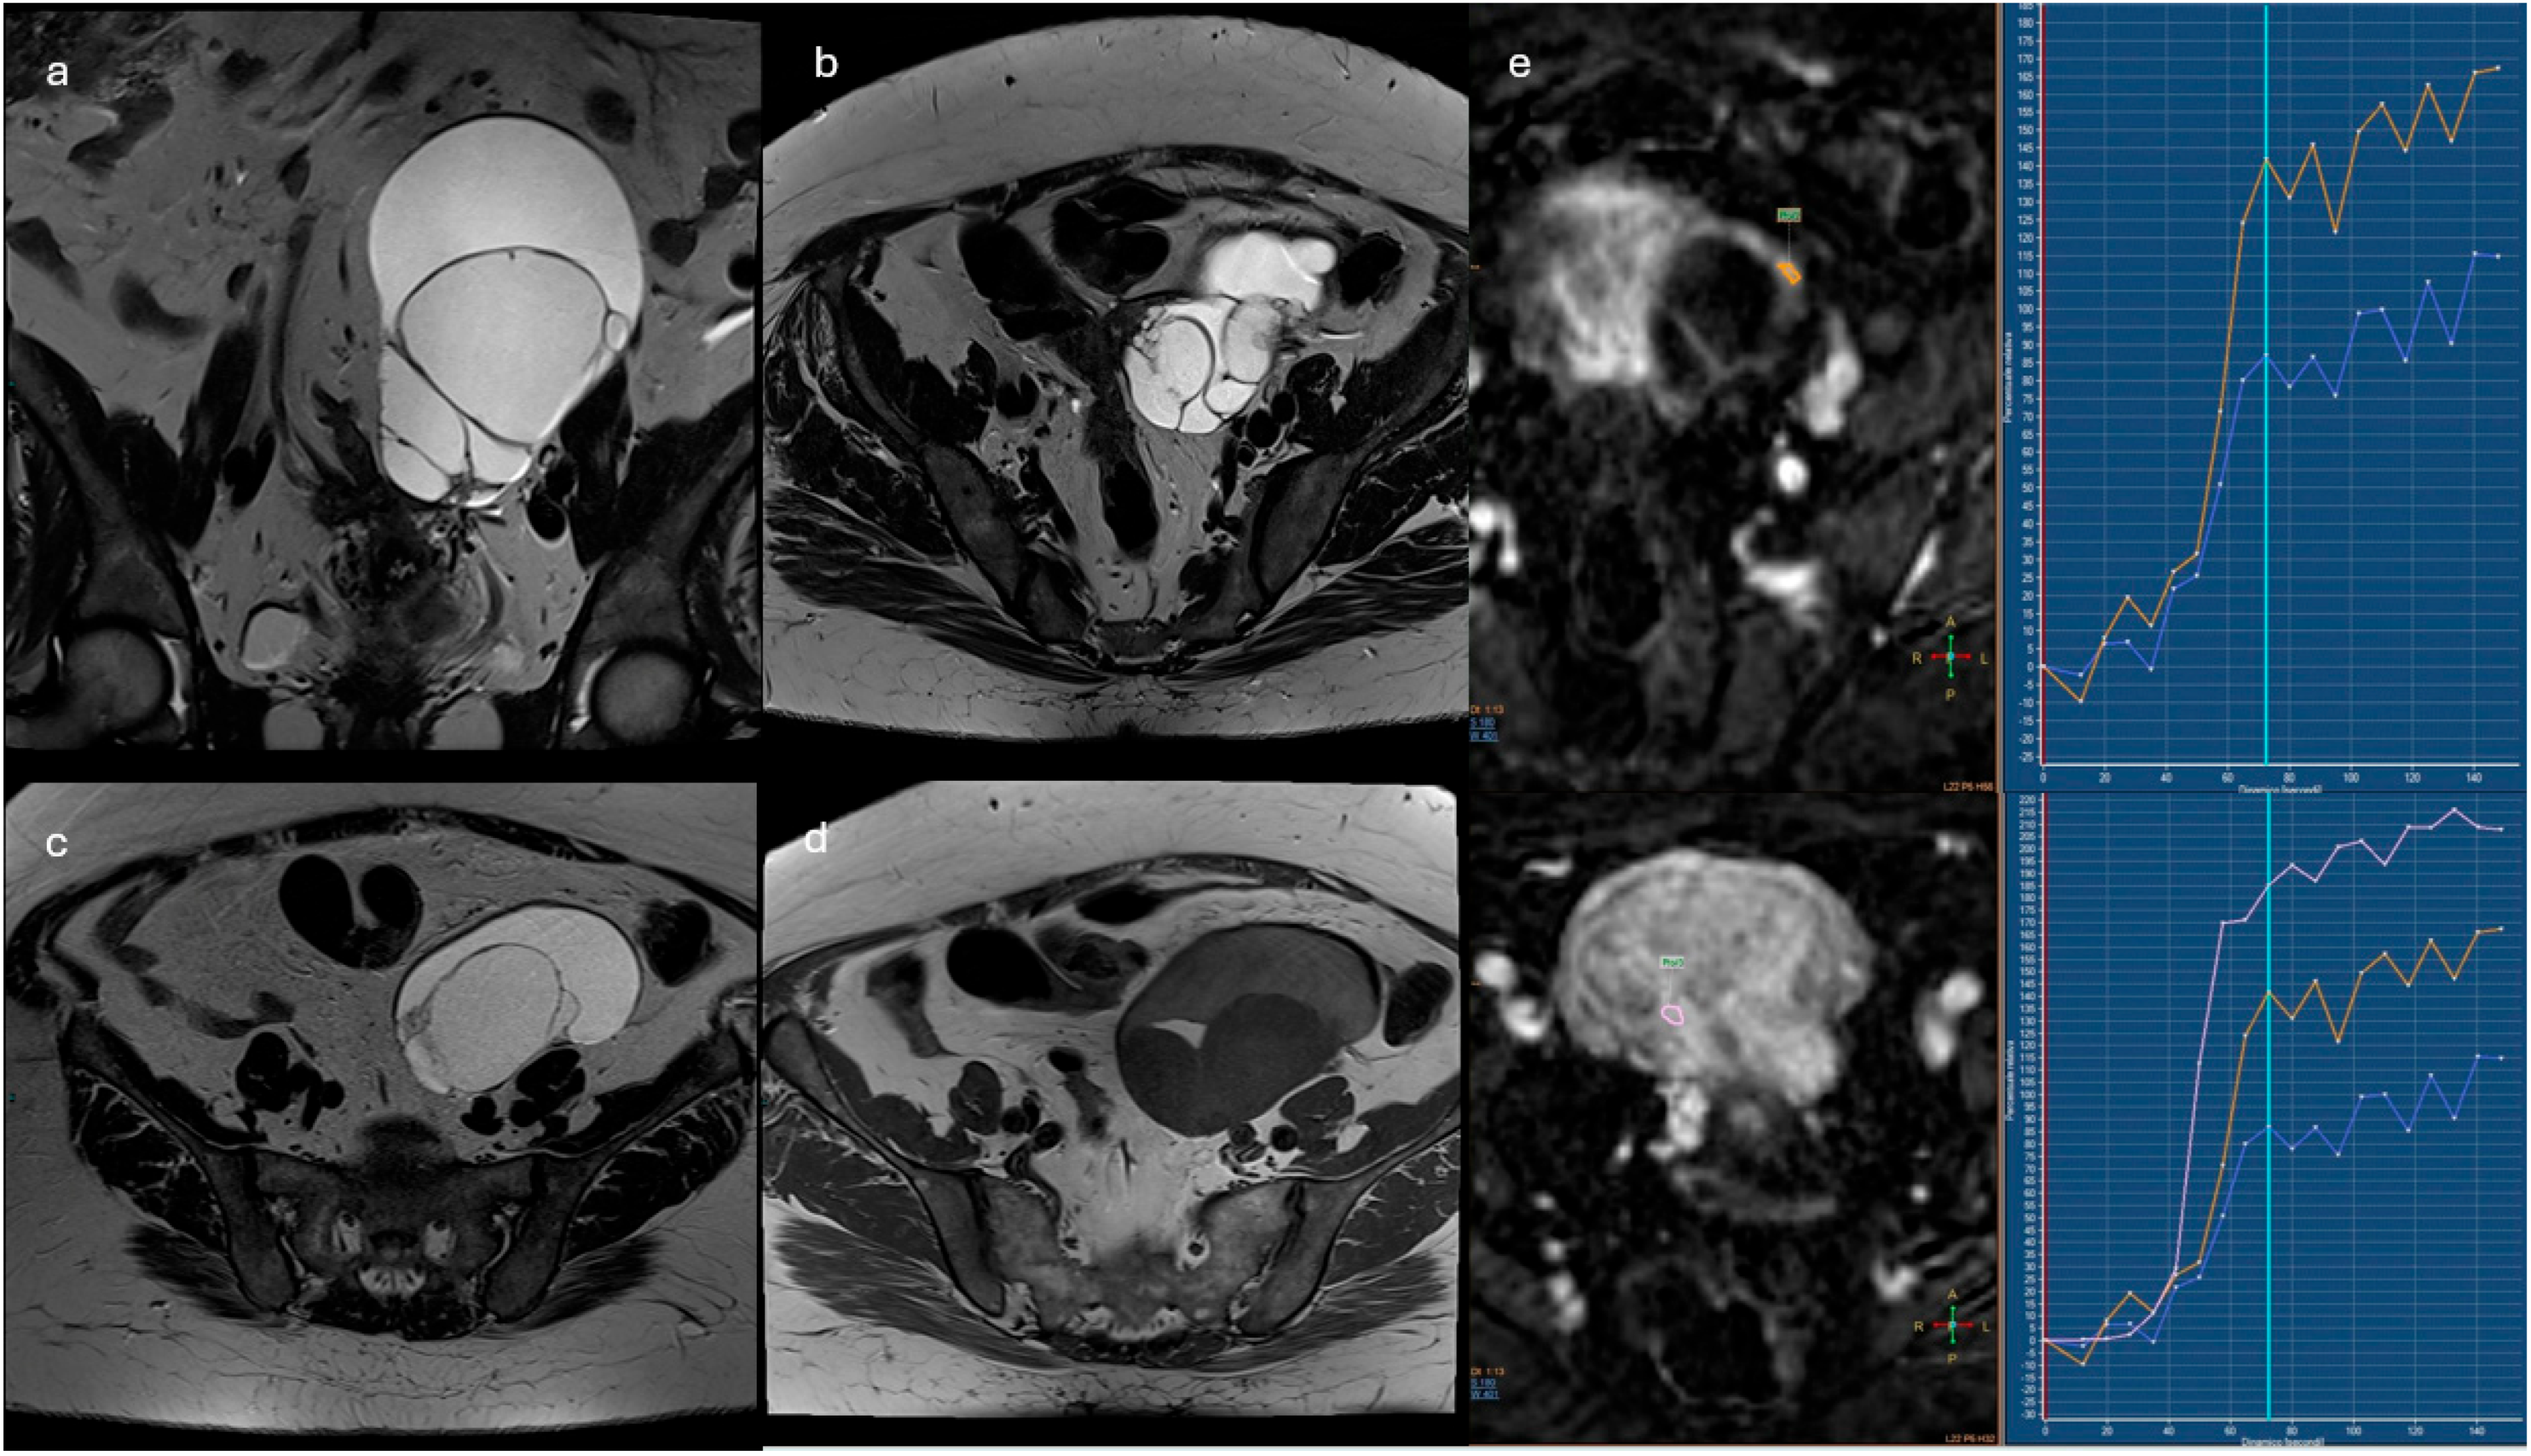

- Lesions with solid tissue (excluding solid lesions described in score 2) showing type 2 enhancement curve (intermediate risk; Figure 5)

- Lesions associated with the presence of peritoneal implants and/or secondary disease localization (Figure 6)